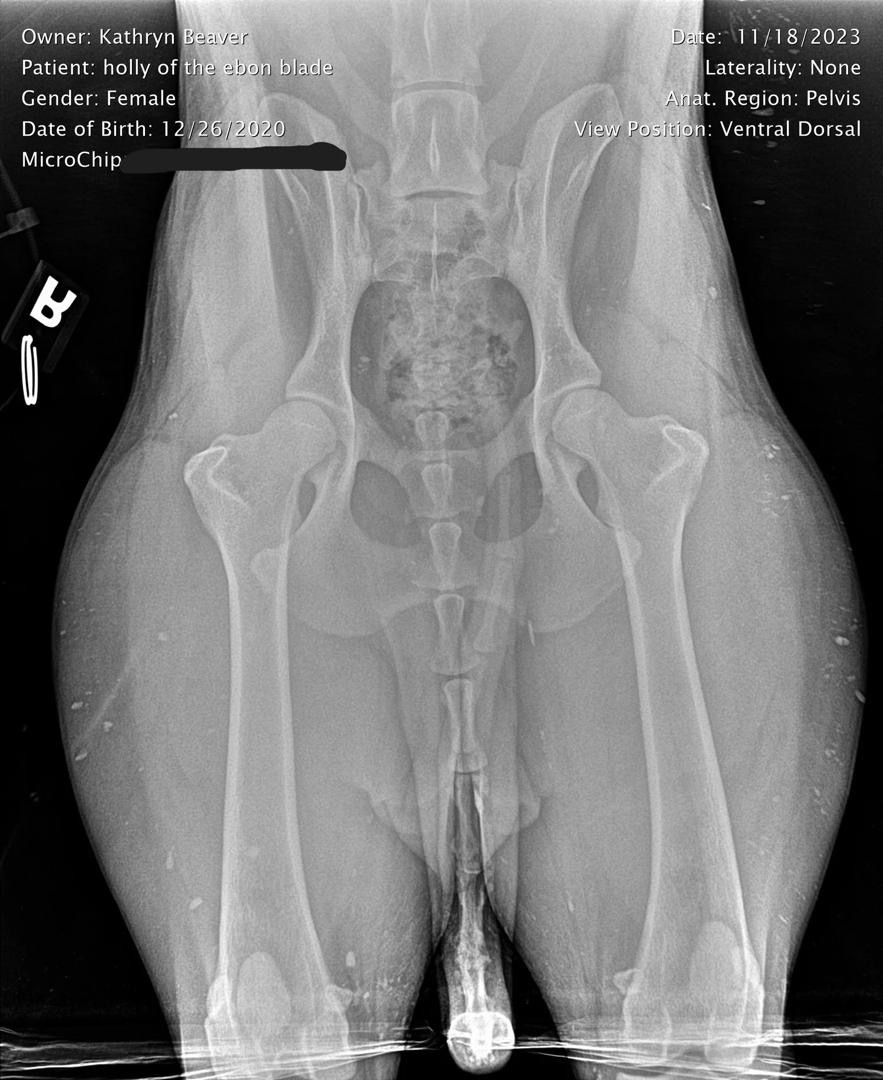

Holly Hip X-Ray

Hip X-Ray Results

OFA Hip Evaluation: Good

Holly's comprehensive health testing demonstrates consistent orthopedic and systemic health that has been maintained throughout her breeding career. Her Good hip rating, combined with normal elbow and patella evaluations, confirms her structural soundness for both performance and breeding. The detailed X-ray documentation provides complete transparency in her health assessment.